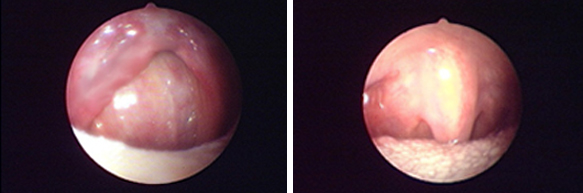

經典案例: